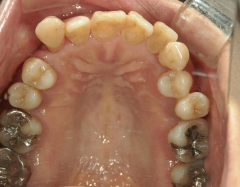

矯正歯科 治療前